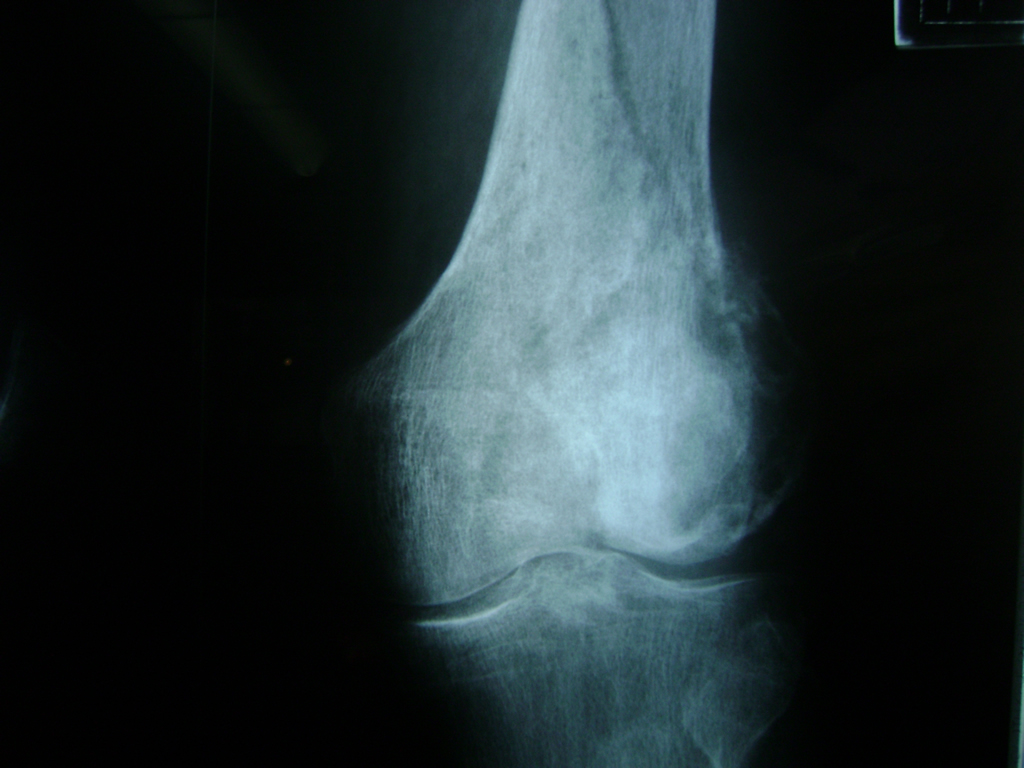

Cirugías de Codos - Rodilla

La artroscopia de rodilla es un cirugía en el cual la estructura interna de la articulación es examinada ya sea para realizar un diagnostico o para realizar un tratamiento, este procedimiento se realiza utilizando un instrumento parecido a un pequeño tubo llamado artroscopio.